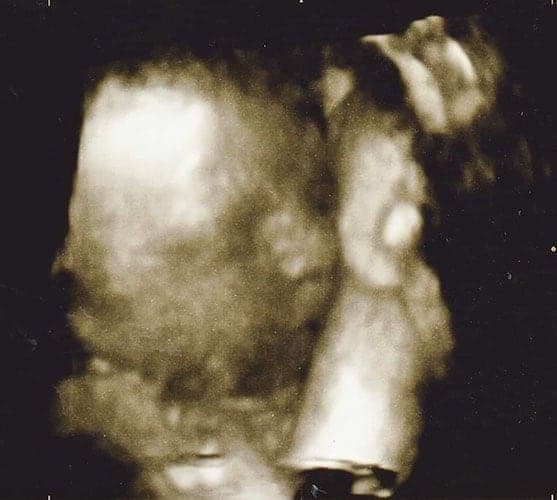

Ultraschallbilder aus dem 3. Trimester (29. bis 40. SSW)

Im dritten Trimester der Schwangerschaft ist das Baby so groß, dass es nicht mehr komplett auf ein Ultraschallbild passt. Nun kann man wunderbare 3D-Ultraschalle des Gesichts machen. In diesem Semester nehmen die Babys nochmal rasant zu und wer Glück hat, kann auf seinem Ultraschall schon erste Gesichtszüge erkennen.

Wer sich jedoch erhofft Gesichtszüge zu erkennen, der wird oft enttäuscht. Zwar kann man beim 3D-Ultraschall schon eine Menge sehen, aber das umgebende Fruchtwasser sorgt in den allermeisten Fällen für starke Störungen.